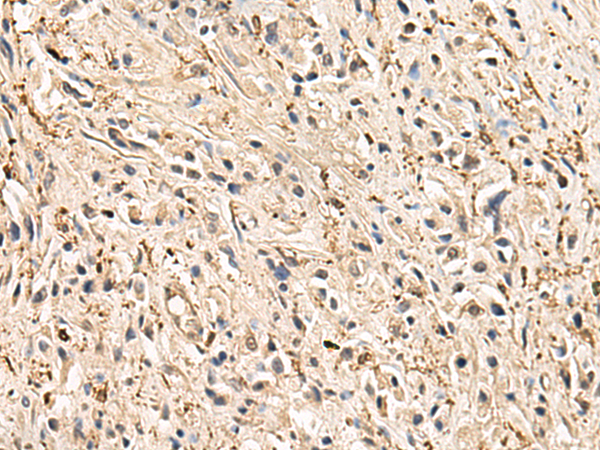

分类: 科研抗体货号: P09880别名: PDIR应用: WB,IHC反应种属: Human, Mouse, Rat